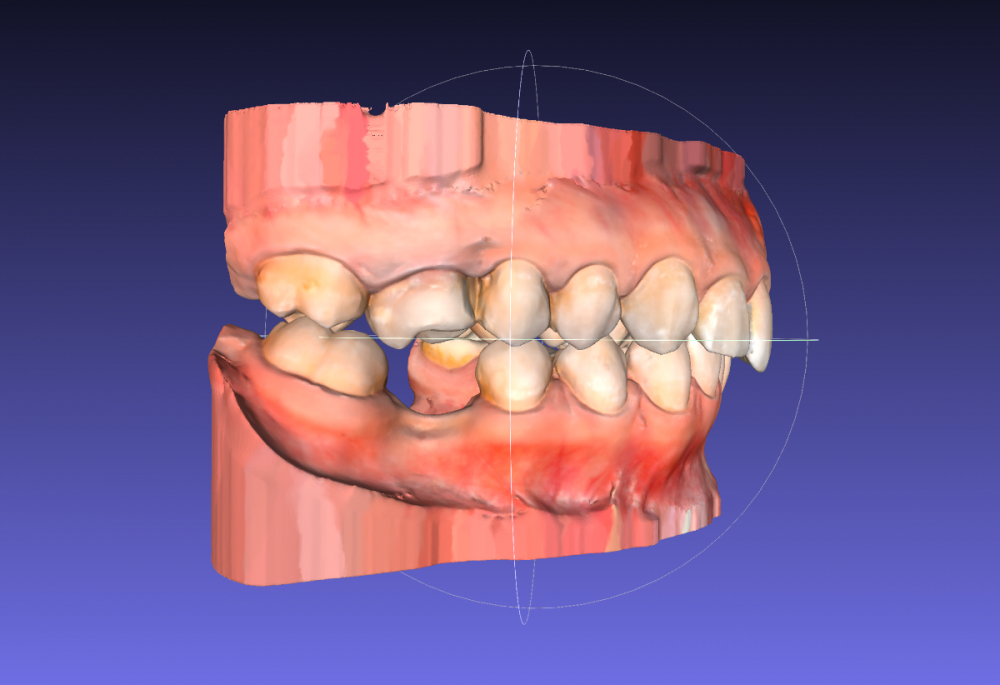

Сейчас я обратилась к ортодонтам с целью выровнять только нижний зубной ряд (искривлен из за воздействия 8ок), с последующей установкой импланта (46 зуб). Нижние восьмерки удалены.

Нужно ли и можно ли двигать верхний ряд?

Лечение планирую исключительно на элайнерах.